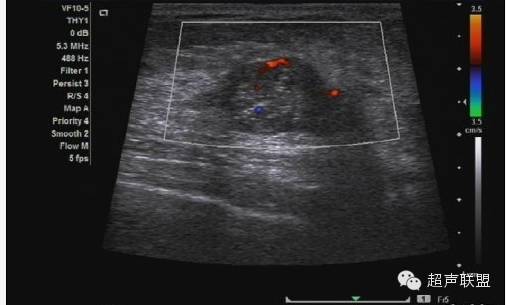

3. 振荡多普勒成像

振荡多普勒成像或声学弹力图,是从著名的震颤乳腺超声技术派生而来的(如图5所示)。在震颤检查中,用彩色或功率多普勒进行乳腺成像的同时要求病人发出声音。乳腺中松软的部份振动较大,而癌变区域和其它较硬的组织振幅小,形成影像中色彩较弱的区域。这样原来在B超中声学特性一致的区域,因其结构的疏密变得可以区分。振荡弹力图或振荡多普勒成像与此类似,不同的是用一个单独的传感器产生振荡。该传感器可产生不同的振荡频率,而成像系统里的定量功率多普勒算法可以计算出组织在每一频率上的振荡量。振荡多普勒成像用于观察组织的粘弹特性。

对于20个病人的初步研究表明,病变区域的振荡量随频率变化的规律十分复杂。病变肿块区并不是在任一频率都会比周围组织振荡得小。这或许能够解释震颤法临床所得的结果变化不一。不同的病人发出不同的音调,在特定频率下,病变区的振荡不一定与周围组织不同。而且,良性肿块振荡量随频率变化的范围很大。相反癌变区表现出少量的振荡,而且随振荡频率的变化很小。